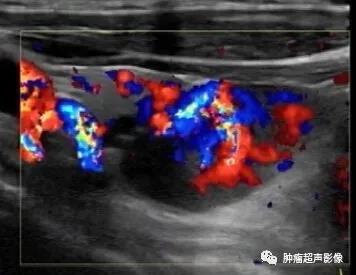

5、血流:一般血流丰富,血流表现为极性特点,由一端进入后呈分支状,或绕行半圈进入,有些血流从上半部分垂直进入(瀑布样),一般无甲状腺腺瘤的环形血流。

病理证实的甲状旁腺腺瘤:位于甲状腺下极旁,完整的包膜,呈低回声,血流丰富且为典型的极性血供,由一端进入后呈分支分布,符合典型的甲状旁腺腺瘤。